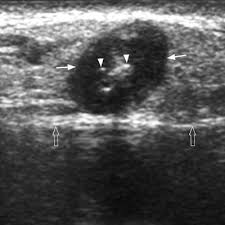

Head and neck cancers include cancers in: There can be more than one sentinel node. I had an ultrasound done in 2012 but the report for this scan never reached my previous doctor's practice and so nothing was. This study was done to evaluate the use of ultrasound to examine lymph nodes in the neck in surgical planning for thyroid cancer surgery and to identify which patients are best served. An ultrasound of the thyroid produces pictures of the thyroid gland and the adjacent structures in the neck. While it can't diagnose cancer, it can detect the abnormal tissues that may possibly be cancerous. The image may or may not suggest cancer, but definitive diagnosis requires removal of. For most types of cancer, a biopsy is the only sure way for the doctor to know if an area of the body has cancer. When ultrasound is performed on a patient with nodular goiter, or a patient with a history of thyroid cancer, finding a prominent lymph node with a rounded shape (long/short axis ratio < 2) and absent hilar line warrants further evaluation of the node (figs. Ultrasounds have many limitations an ultrasound is not good enough for many aspects of cancer. Carotid ultrasound tests for blocked or narrowed carotid arteries, which can increase the. Confirming that a lump in the neck is developing from the thyroid or connected tissue. Spread of thyroid cancer to the lymph nodes in the neck is common and increases the risk of cancer recurrence.

Figure 3 From Post Thyroidectomy Neck Ultrasonography In Patients With Thyroid Cancer And A Review Of The Literature Semantic Scholar from d3i71xaburhd42.cloudfront.net Ultrasound is often one of the first line tests in the detection of cancer. These tests can also show whether a nodule is toxic or producing too much thyroxine, causing hyperthyroidism. Spread of thyroid cancer to the lymph nodes in the neck is common and increases the risk of cancer recurrence. I was officially diagnosed hashimoto's by my endocrinologist 2 weeks ago but she has refused to do an ultrasound of the thyroid. 8.4, 8.5, 8.6, 8.7, and 8.8). An ultrasound of the neck is used to examine the carotid arteries located on each side of a patient's neck. Our doctors also use ultrasound to check lymph nodes in the neck, where some forms of thyroid cancer can spread. It can be used with a fine needle aspiration test or core biopsy test to accurately direct the tip of the needle into the lump.

Carotid ultrasound tests for blocked or narrowed carotid arteries, which can increase the. Some of the indications for thyroid or neck ultrasound are thyroid nodules, goiter, thyroid cancer and other neck masses. Expert ultrasound can also help confirm a diagnosis of papillary thyroid cancer which has spread to the lymph nodes of the neck. It can detect abnormal tissues, growths, and cysts and give a suspicion of cancer based on how those images look. Ultrasound is widely available an is useful to identify abnormal lymph nodes that may contain cancer.

People may use the word throat to describe different parts of the neck. Your two carotid arteries are located on each side of your neck. A neck ultrasound can be used to observe the thyroid gland to look for nodules, growths, or tumors. Although many unskilled observers would believe that size is a major issue, but it actually is not. Lymph nodes are part of the lymphatic system, which helps to protect us from infection and disease. If this happens, it is called metastasis. Part of the throat (cancers of the oropharynx and tonsils, nasopharynx and hypopharynx) the nose or sinuses (nasal and sinus cancer) the salivary glands. If the person has a lump in the neck, an fna can show if the mass is from cancer spread. The expert ultrasonographer will look for multiple changes. While it can't diagnose cancer, it can detect the abnormal tissues that may possibly be cancerous. Ultrasound guidance is used to perform thyroid biopsies and improves the diagnostic accuracy of fine needle biopsy. If this lump is of concern then a biopsy would be the next step. An ultrasound of the neck is used to examine the carotid arteries located on each side of a patient's neck.